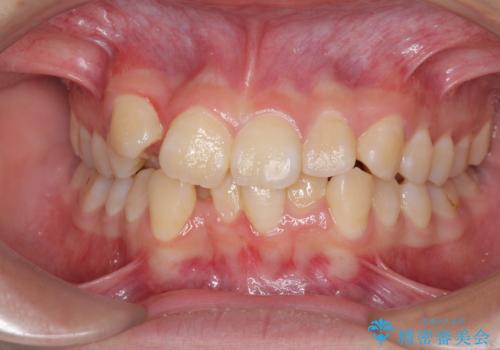

八重歯がスッキリ 抜歯ワイヤー矯正

担当医 今村大二郎

八重歯が気になる ワイヤーによる抜歯矯正できれいな歯並びへ